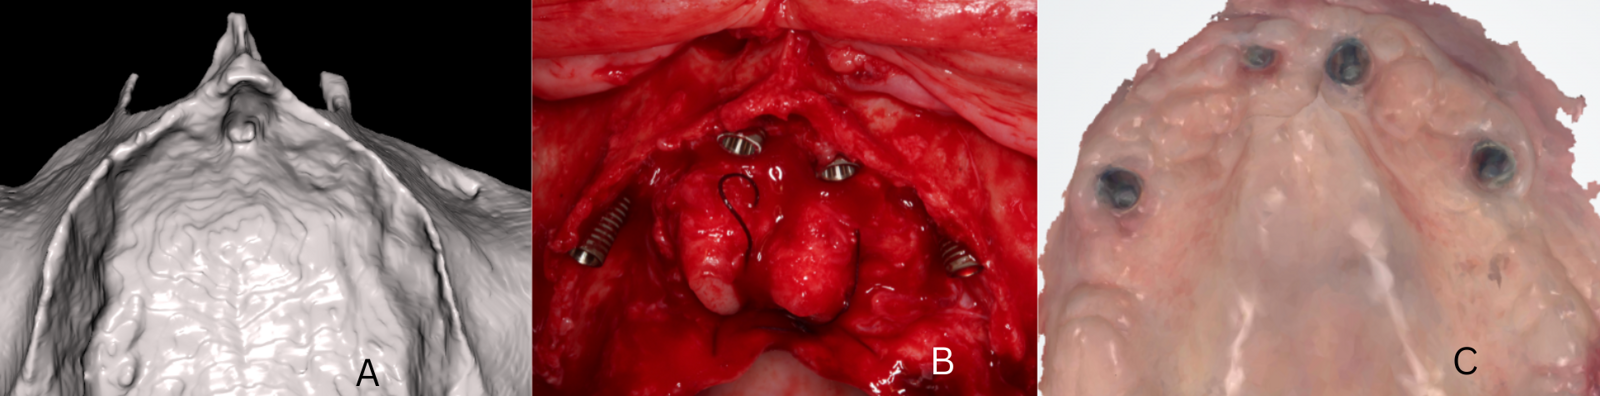

Implantaten met remote verankering onderscheiden zich van conventionele implantaten doordat het implantaat oppervlakte niet in zijn geheel procent in contact staat met het alveolaire bot. In tegenstelling tot het klassieke uitgangspunt dat het implantaat volledig omgeven moet zijn door bot, wordt bij remote verankering slechts het apicale deel van het implantaat in het zeer dense corticale basale bot verankerd, terwijl het coronale gedeelte van het implantaat langs de wand van de processus alveolaris, langs de sinus maxillaris wand, in een corticale fossa of zelfs deels met zacht weefsel in contact komt (figuur 1).

Een voorbeeld van implanteren via een palatinale benadering (palatal approach) bij een zeer ernstige horizontale geresorbeerde kaak (A). De implantaten bevinden zich apicaal geheel in dens nasale bot. Coronaal liggen de implantaten bloot aan de palatinale zijde en worden met dikke palatinale gingiva bedekt (B). Na 3 maanden zijn de multi-unit abutments omringd door gezonde gekeratinseerde gingiva (C).

Dit vormt in de praktijk geen nadeel zolang de primaire apicale stabiliteit hoog is, het coronale gedeelte goed bedekt wordt met een dik stuk aangehechte gingiva, de implantaten aan elkaar verblokt worden door een vaste prothetische voorziening en alle implantaten immediaat worden belast. De functionele stabiliteit komt voort uit de corticale grip van het ankerbot, vaak veel sterker dan de oorspronkelijke alveolaire structuur ooit was, en uit het verblokkingseffect van de implantaten aan elkaar om de buigkrachten tegen te gaan. Die eigenschap maakt zygoma-, pterygoïde, transnasale en transsinusale implantaten tot een betrouwbare oplossing bij ernstige atrofie in de bovenkaak.

Palatinale implantaten Bij palatinale implantaten (palatal approach) wordt het implantaat bewust meer palatinaal geplaatst om de dunne buccale botwand intact te houden en zo een stabielere botverankering te verkrijgen. In deze situatie bevindt het implantaat zich alleen apicaal volledig in het bot, terwijl het coronaal gedeeltelijk buiten het bot ligt aan de palatinale zijde en dus niet geheel door bot wordt omringd. De implantaten variëren, net als gekantelde implantaten, in lengte tussen 10-25 mm en kunnen een gladde kraag hebben, net zoals bij zygoma-implantaten het geval is. Klinisch is het dan belangrijk om de coronale blootliggende implantaatdelen adequaat te managen, bijvoorbeeld door guided bone regeneration (GBR) en/of een zachteweefselverdikking, zodat alsnog een stabiele peri-implantaire weefselomgeving ontstaat. Die aanpak kan voorspelbaar zijn, mits er apicaal voldoende botcontact aanwezig is voor stabiliteit en er zorgvuldig wordt gewerkt aan het behoud van de biologische breedte en een gunstig emergence profile. Deze techniek kan zeer waardevol zijn, vooral omdat horizontale resorpties veel frequenter voorkomen dan verticale reosorpties bij patiënten die langdurig prothese dragen (figuur 1).8